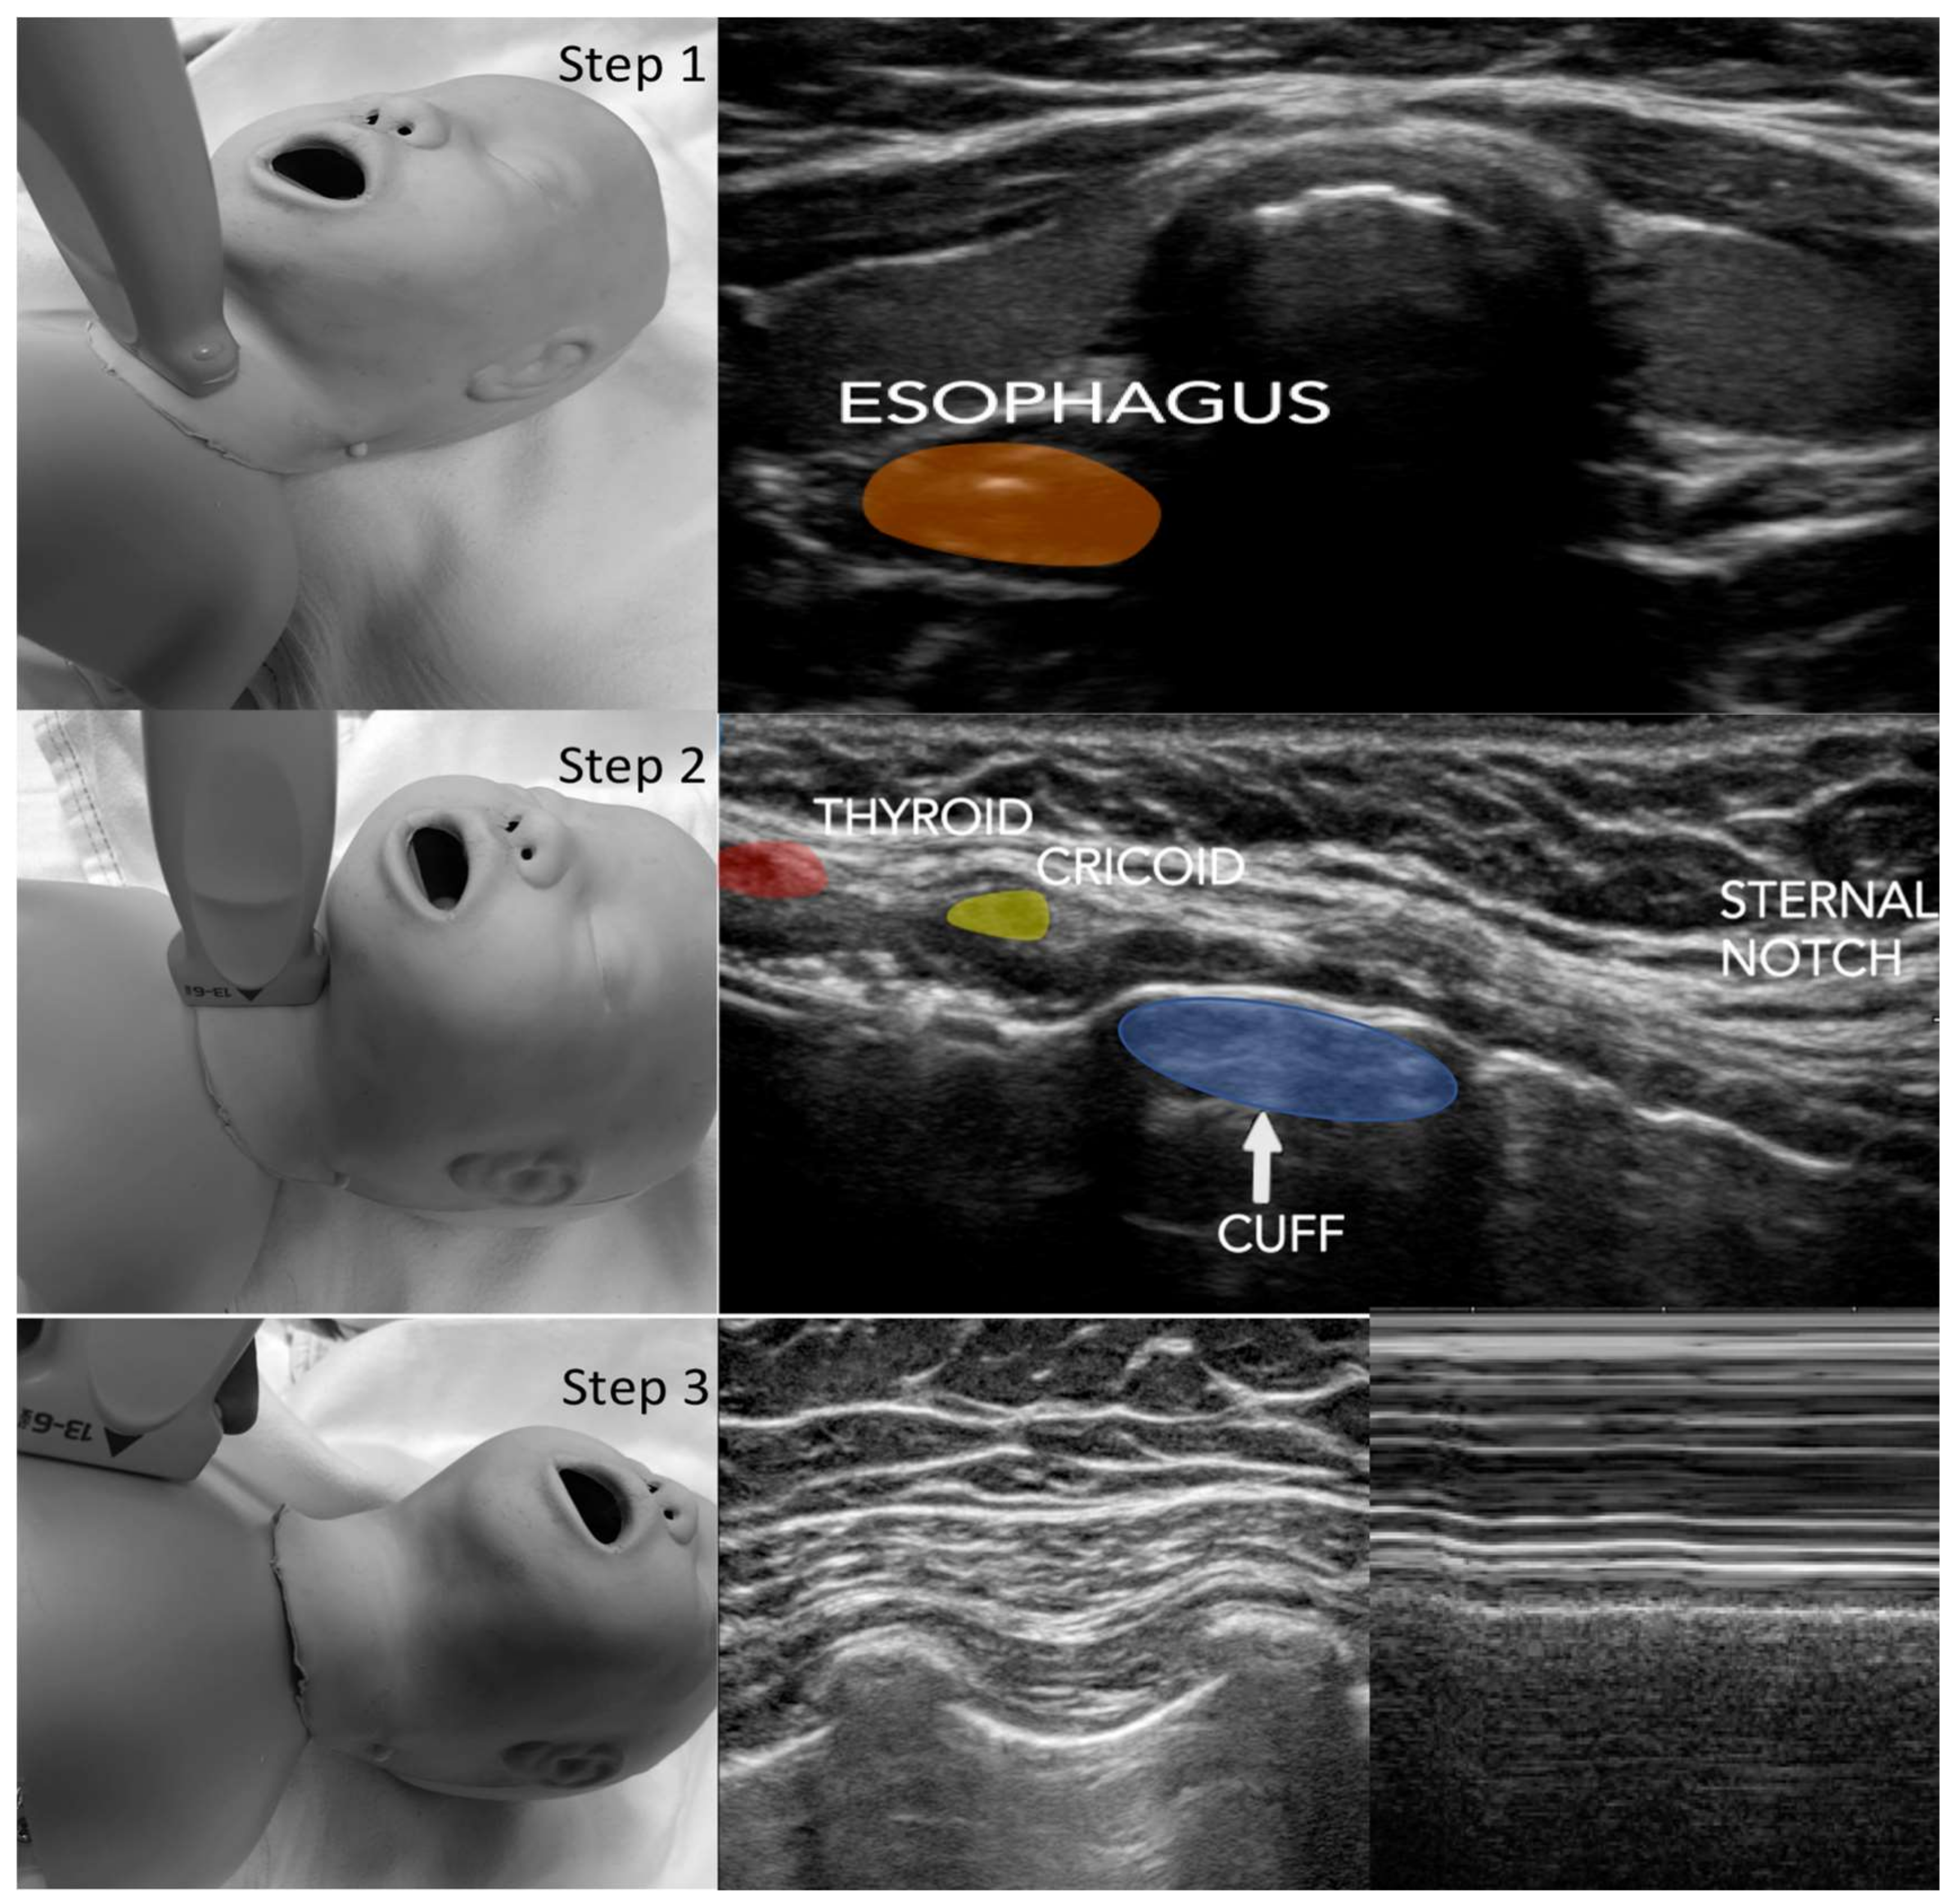

2.2. Protocol

2.3. Data Acquisition